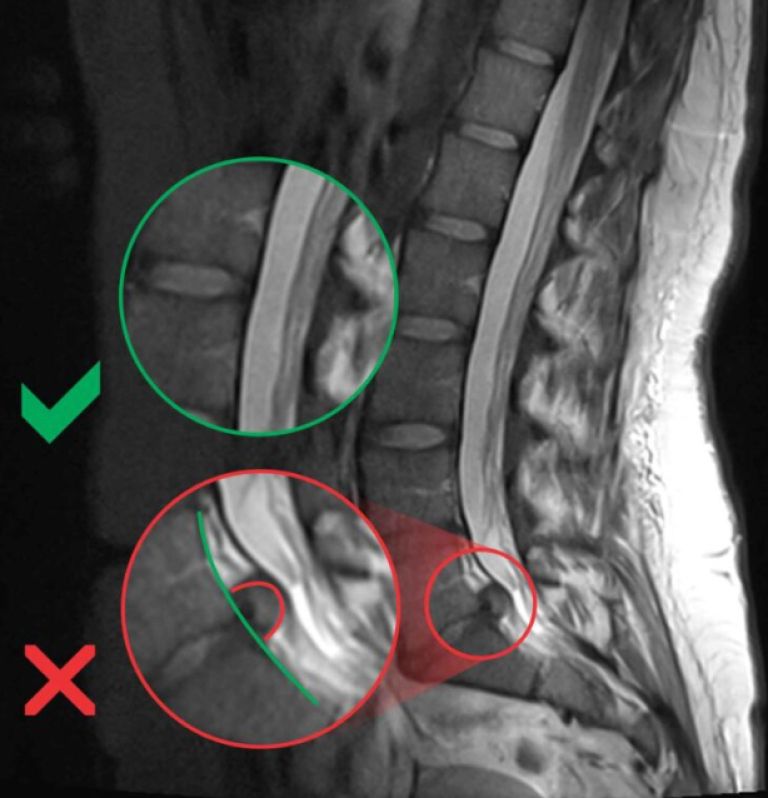

Hernija diska nastane, ko mehko jedro medvretenčne ploščice (nucleus pulposus) prodre skozi trd zunanji obroč (anulus fibrosus). To lahko povzroči pritisk na okoliške živce, kar vodi do bolečin in drugih simptomov. Najpogostejši vzrok za nastanek hernije diska je staranje in s tem povezana degeneracija medvretenčnih ploščic. S starostjo ploščice izgubljajo vodo in postajajo manj prožne, kar povečuje tveganje za hernijo.

Za diagnozo hernije diska zdravniki običajno najprej opravijo fizični pregled in pregledajo pacientovo anamnezo. Če je potrebno, lahko predpišejo dodatne diagnostične teste, kot so magnetna resonanca (MRI), računalniška tomografija (CT) ali rentgensko slikanje. Ti testi pomagajo natančno določiti lokacijo in resnost hernije diska.